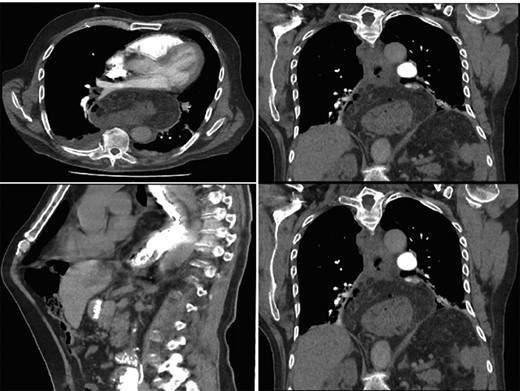

Interval gastroscopy in 2 weeks showed healing mucosal ischemia with slough from 27–30 cm (Fig. 3). Clear fluids were commenced and gradually upgraded to normal diet. Follow-up CT showed no contrast extravasation within posterior mediastinum (Fig. 4) and gastroscopy in 8 weeks showed healed esophagus.

Healing mucosal ischemia from upper, mid and distal esophagus.